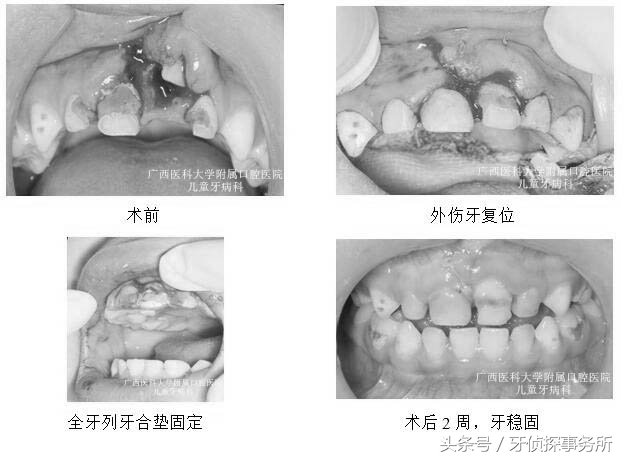

1、部分脱位

碰撞后乳牙在外力的作用下向外或向内倾斜移位后部分脱出牙槽窝时,可将外伤牙恢复到原位后结扎固定,一般预后较好,但日后有可能发生牙髓坏死,根尖感染或牙槽脓肿。如果接近替牙期或者乳牙牙根已吸收1/2以上者可以考虑拔除该颗松动乳牙。

3、嵌入性脱位

嵌入,即牙齿陷入牙槽骨。如果伤及恒牙牙胚需要将嵌入的乳牙复位;如果是在替换牙期,可以将嵌入的乳牙拔除;其他情况可以不必处理,等乳牙自行长出。